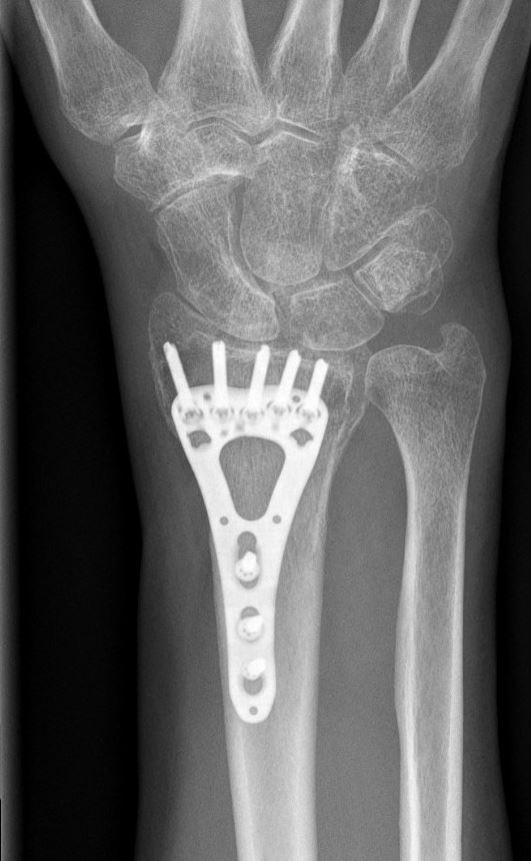

Operatie bij volwassenen

Indien er sprake is van een ernstige breuk met een slechte stand (ondanks zetten) of wanneer wordt ingeschat dat de stand van de breuk nog verder zal verslechteren, dan kan de traumachirurg samen met u bepalen dat er een indicatie is voor een operatie. Hiervoor zijn er meerdere opties. Het meest wordt er gebruik gemaakt van een plaatje en schroeven voor het vastzetten van de breuk. Soms wordt er ook gebruik gemaakt van stevige staaldraden of van een fixatie aan de buitenkant (zogenaamde ‘externe fixateur’).

Zoals elke operatie, heeft ook een operatie voor een gebroken pols kans op complicaties, zoals ontstekingen van de wond, pijnklachten, pees-, vaat- of zenuwletsel en het loslaten van het fixatie materiaal en het alsnog verplaatsen van de breuk. Welke operatie u krijgt, is afhankelijk van de eigenschappen van de breuk en de toestand van de huid en de spieren. Uw traumachirurg bepaalt of het nog nodig is om na de operatie nog tijdelijk gips te krijgen.